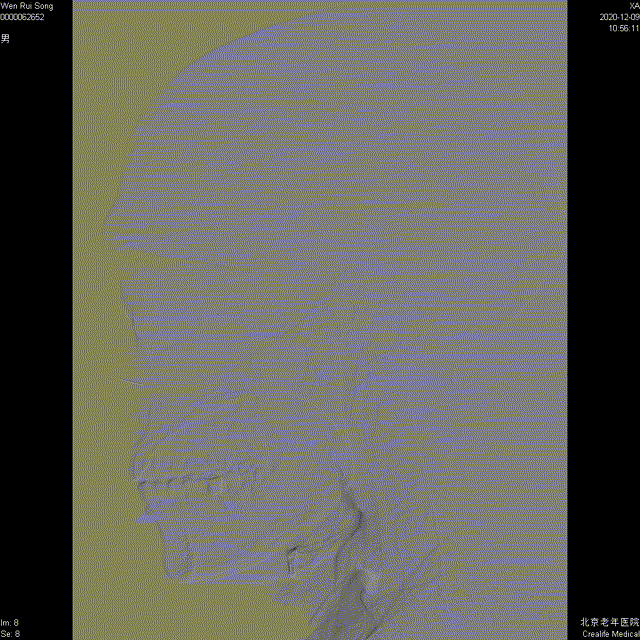

这是颈动脉正位与侧位图,从图中可以看到脑血管造影可以动态、清晰、多方位、多角度的显示血管。